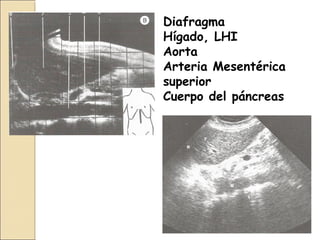

Corte longitudinal paramedialCorte longitudinal paramedial

izquierdoizquierdo

Diafragma

Hígado, LHI

Aorta

Arteria

Mesentérica

superior

Cuerpo del

páncreas

Diafragma

Hígado, LHI

Aorta

Arteria Mesentérica

Cuerpo del páncreas